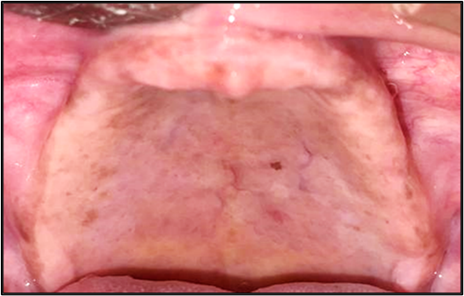

Figure 1: Flabby Anterior Maxillary Ridge.

The rehabilitation of completely edentulous patients remains a clinical challenge, particularly in the presence of compromised ridge condition such as flabby tissues. According to Glossary of Prosthodontic Terms (GPT) 9-Flabby tissue is defined as excessive, movable tissue. Flabby tissue or hypermobile ridge tissue is commonly seen in the anterior part of the edentulous maxillary ridge or an atrophic knife-edge mandibular ridge which adversely affect the support, stability and retention of conventional dentures. It is commonly associated with long-term denture wear, traumatic occlusion or residual ridge resorption. Successful management requires accurate impression techniques that record the flabby tissues without distortion, thereby ensuring optimal prosthesis function and patient comfort.

A 58-year-old female, presented with complaint of constant dislodgement of her denture during chewing, accompanied by significant difficulty in chewing food over the past eight months. Her dental history showed a gradual loss of teeth spanning approximately seven years, with complete edentulism established six years ago. A pre-treatment panoramic radiograph revealed generalized alveolar bone resorption, more pronounced in the mandibular ridge. The maxillary alveolar ridge exhibited moderate resorption, with diminished bone height particularly in the anterior region corresponding to the flabby premaxillary tissue. A conservative, non-surgical prosthodontic rehabilitation was planned.